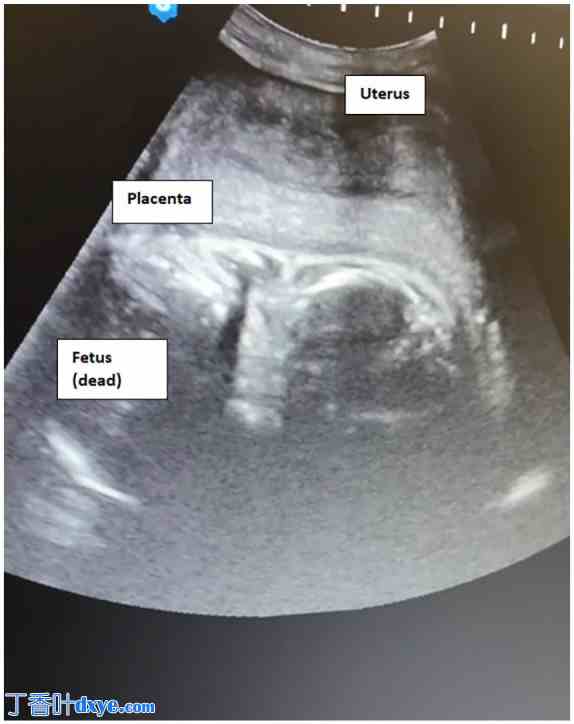

体格检查显示患者神志清醒,配合医生,定向力良好,面色苍白,卫生习惯不良。患者无发热,但心动过速。腹部柔软,膨隆,弥漫性压痛。阴道点滴出血。床边超声检查发现胎儿无法存活,但找不到胎盘。盆腔检查发现宫颈闭合。随后,作者的母婴医学专家将她转诊至正式的超声检查。超声检查证实了妊娠 25 周无法存活。然而,她的妊娠并非宫内。子宫看起来是空的。胎儿和胎盘均位于子宫后部,羊水不足(图 1)。还观察到大量腹腔积液到达 Morrison 袋,并解释为腹腔积血(图 2)。紧急安排了剖腹手术。检查显示白细胞增多(WBC 计数 = 18 × 109/L)、C 反应蛋白升高(CRP = 300 mg/dl)以及妊娠中期妇女的正常血红蛋白水平(Hb = 11.1 g/dl)。

图 1.

经腹超声检查。胎儿和胎盘位于空子宫后方。